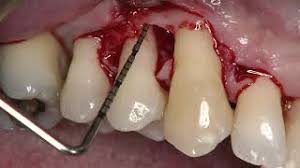

- The Single Flap Approach Step-by-Step Application. How Should You Manage the Flap, the Defect and the Root? (29:46 min)